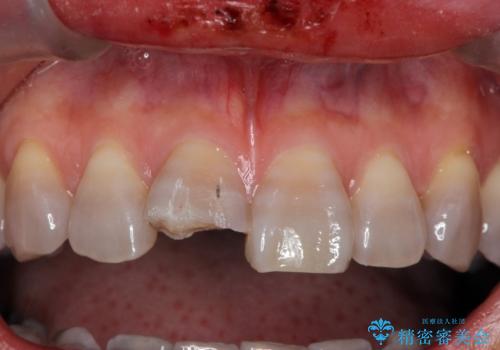

転んで前歯が折れた 色合いの難しい歯のセラミック修復

- 転倒し前歯を地面に強打して折れたとのことで来院。

幸い神経は生きており、セラミックでかぶせることになりました。

まず保険治療でコンポジットレジン修復を行い、神経の状態を確認した後、クラウンによる修復を行いました。